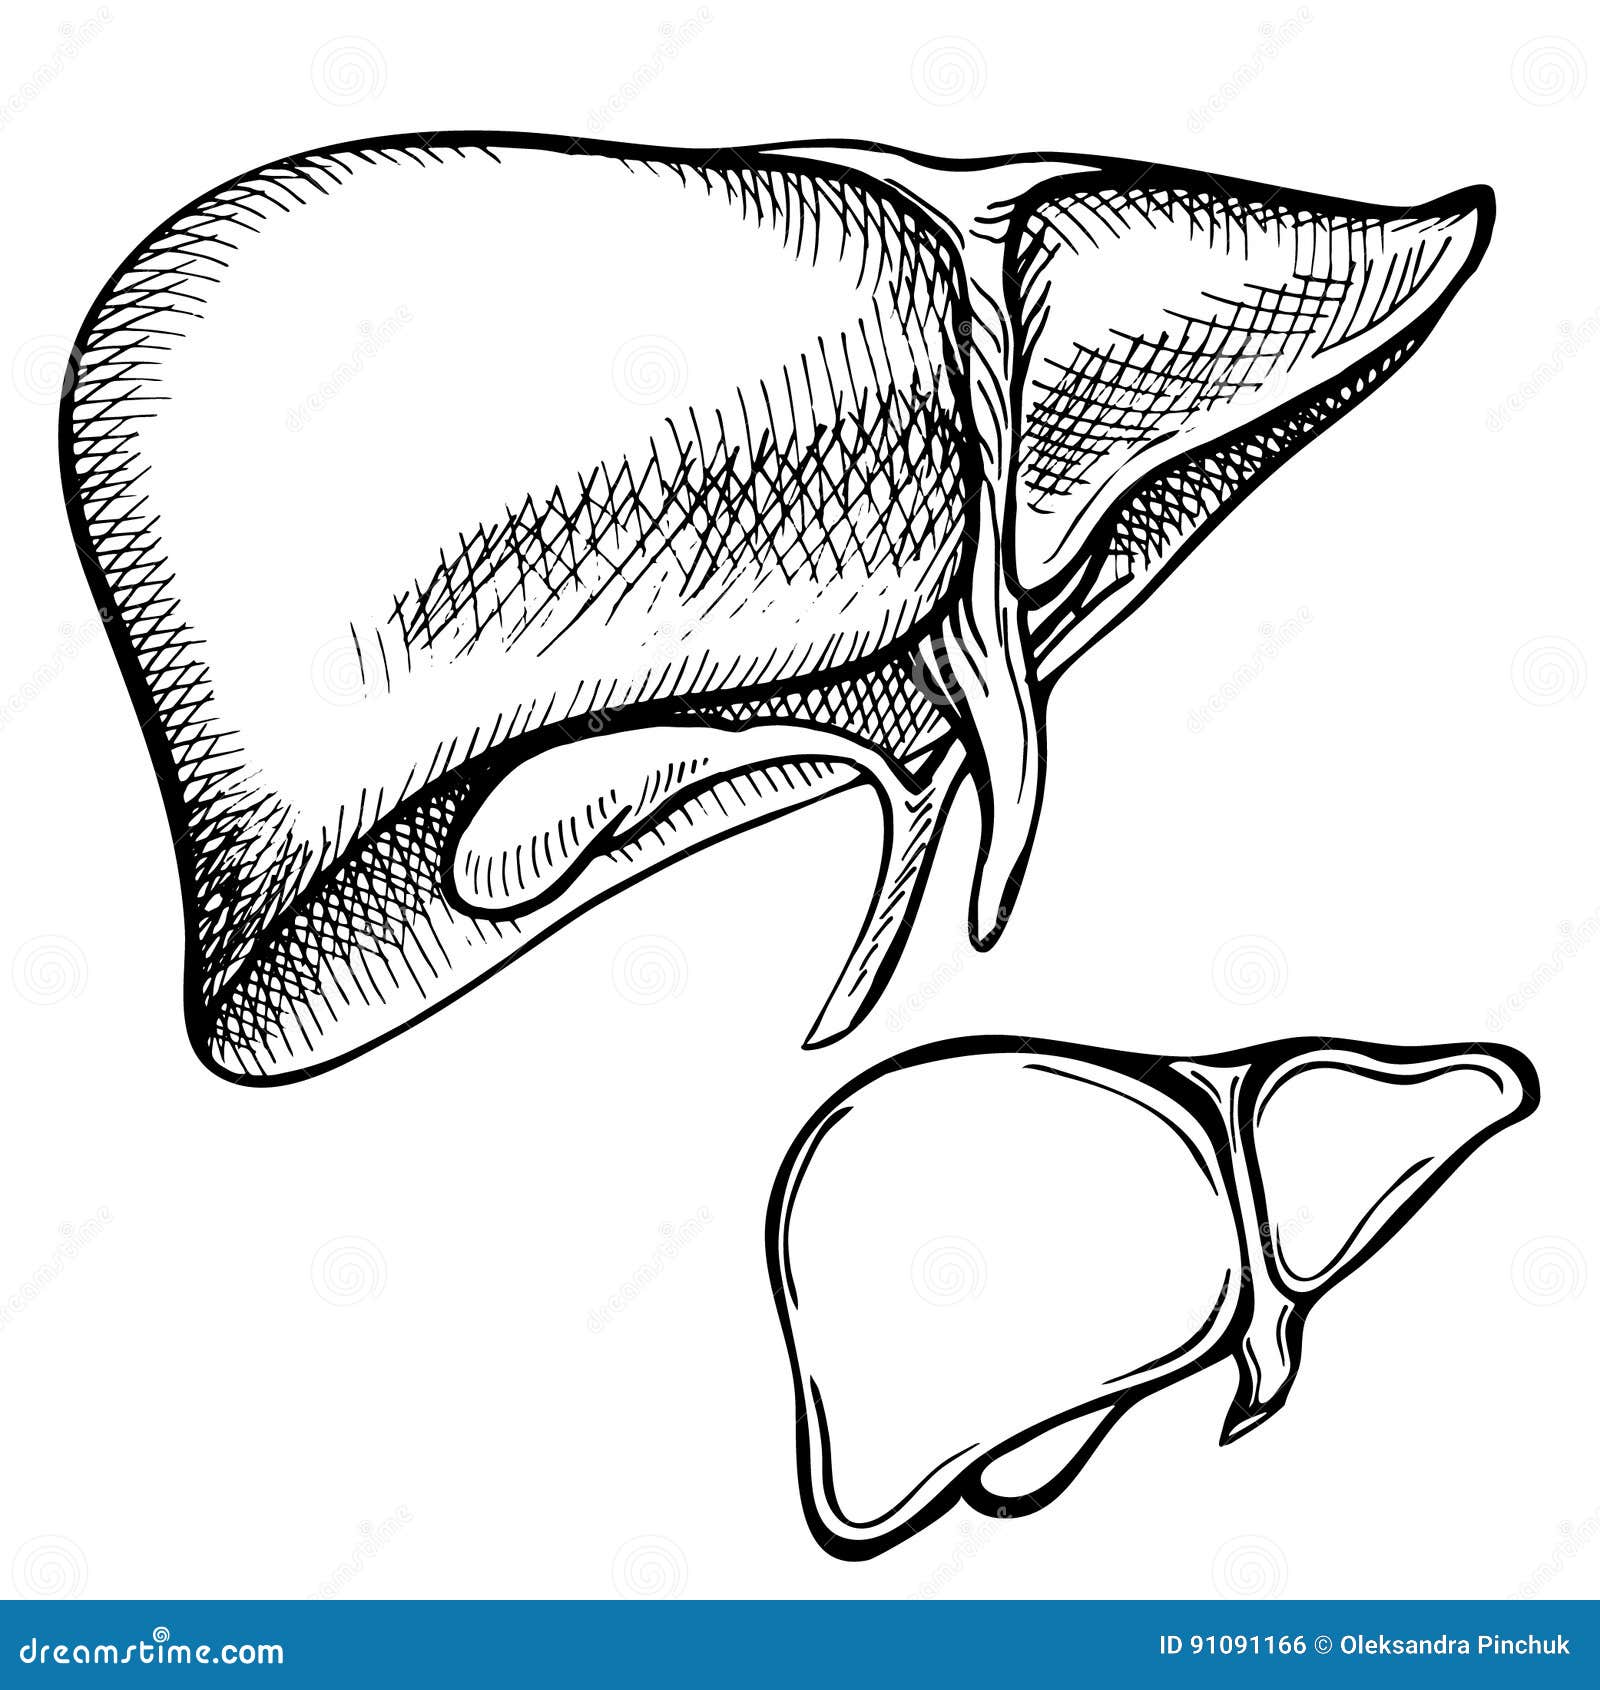

Печень, один из самых крупных и важных органов человеческого тела, выполняет множество жизненно необходимых функций, включая фильтрацию токсинов и производство жизненно важных белков. В данной статье мы рассмотрим, как наглядные изображения печени могут помочь лучше понять её структуру, функции и возможные заболевания. Использование рисунков и диаграмм делает сложные биологические процессы более доступными для понимания, особенно важно это для студентов, врачей и пациентов, стремящихся глубже изучить этот ключевой орган.

Печень рисунок